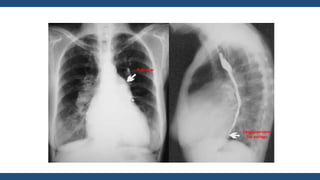

Radiografía de

Tórax

• Corazón generalmente de tamaño normal

• Perfil izquierdo con 4 arcos

• Aorta

• Pulmonar abombada

• Orejuela Izquierda prominente

• Ventrículo Izquierdo Normal

• En posiciones oblicuas

hay crecimiento de la AI

• Signos radiológicos de

hipertensión venocapilar

Moteado difuso

Hilios Pulmonares

Esfumados

Lineas A de Kerley

Lineas B de Kerley

Derrame Laminar

Infiltrados algodonosos

Guadalajara, J. F. (2012). Cardiología. CDMX: Mendez Editores.